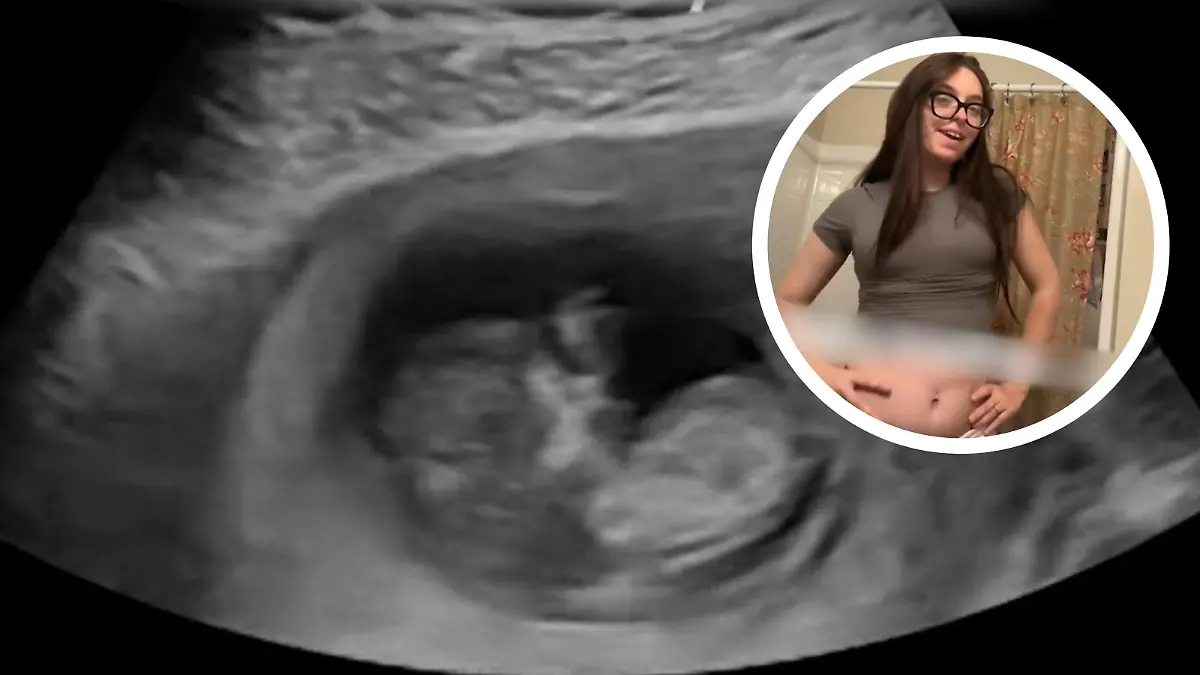

SchwangerschaftEine Schwangerschaft ist eine besondere Zeit: Ein Kind entsteht. Starke körperliche Veränderungen und unterschiedlichste Emotionen prägen den gesamten Schwangerschaftsverlauf.Ärzte bemerkten viermal ihre Schwangerschaft nicht! Zoe und ihre ungeborene Tochter totNachrichtenSchamlos! Porno-Star Bonnie Blue gesteht Fake-SchwangerschaftStar News„Let’s Dance”-Profi Andrzej Cibis wird wieder Papa!ShowsSo schön schwanger! Jeanette Biedermanns erster TV-Auftritt mit BabybauchStar NewsDas nächste Weltmeister-Baby ist da!SportSavannah Miller ist schwanger mit 47Star NewsSorge um Babys? Bundestag prüft heikle Bluttests neu!NachrichtenSorge um Babys? Bundestag prüft heikle Bluttests neu!NachrichtenVideo [ 1:22 ] • Jetzt ansehenSchwanger mit 46! Jetzt zeigt uns Jeanette Biedermann ihren BabybauchStar NewsHier verkünden die Adamyans das Geschlecht ihres WunderbabysStar NewsWarum wir bei Vornamen eine Generation überspringenBesser LebenBaby-News bei Andrej Mangold und seiner AnnikaStar NewsErst Verlobung, jetzt Vaterfreuden! DIESER Ex-Bachelor wird bald PapaStar NewsVideo [ 0:41 ] • Jetzt ansehenErstes Baby mit 46! Jeanette Biedermann ist schwangerStar NewsDenise Merten und Mann Henning machen Fehlgeburt öffentlich Star News12345678910111213141516171819202. Trimester1. Trimester